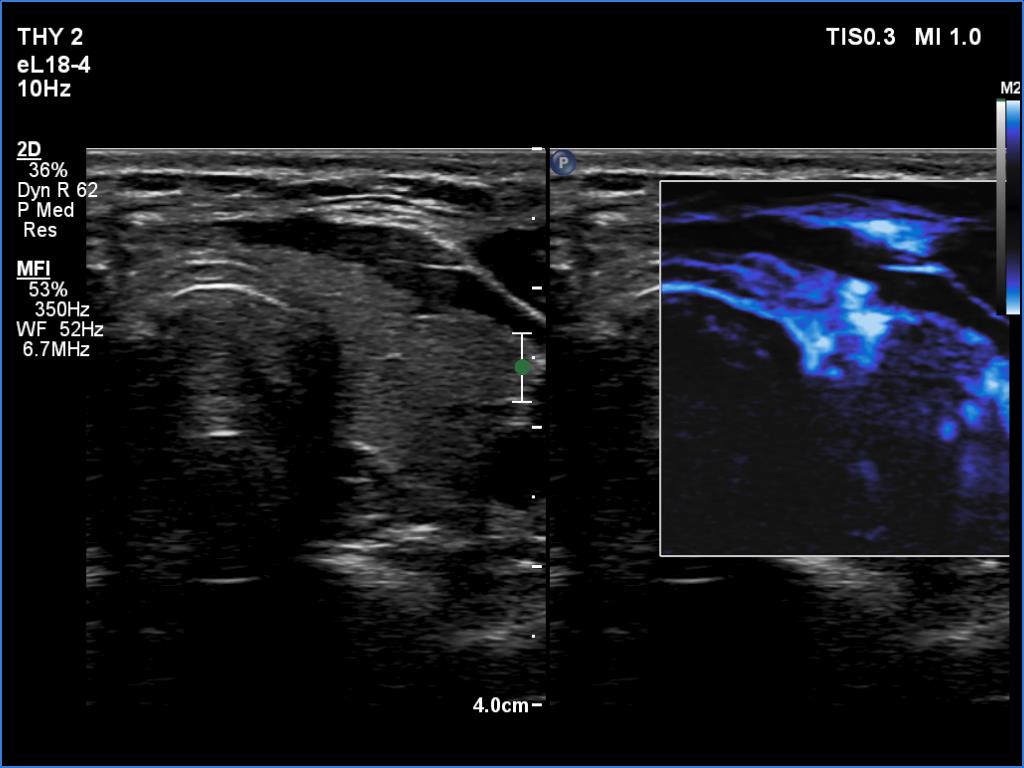

The operated thyroid - case 1641

Four weeks after the surgery (ultrasonographic picture 8)

Left lobe, transverse scan, microflow imaging.